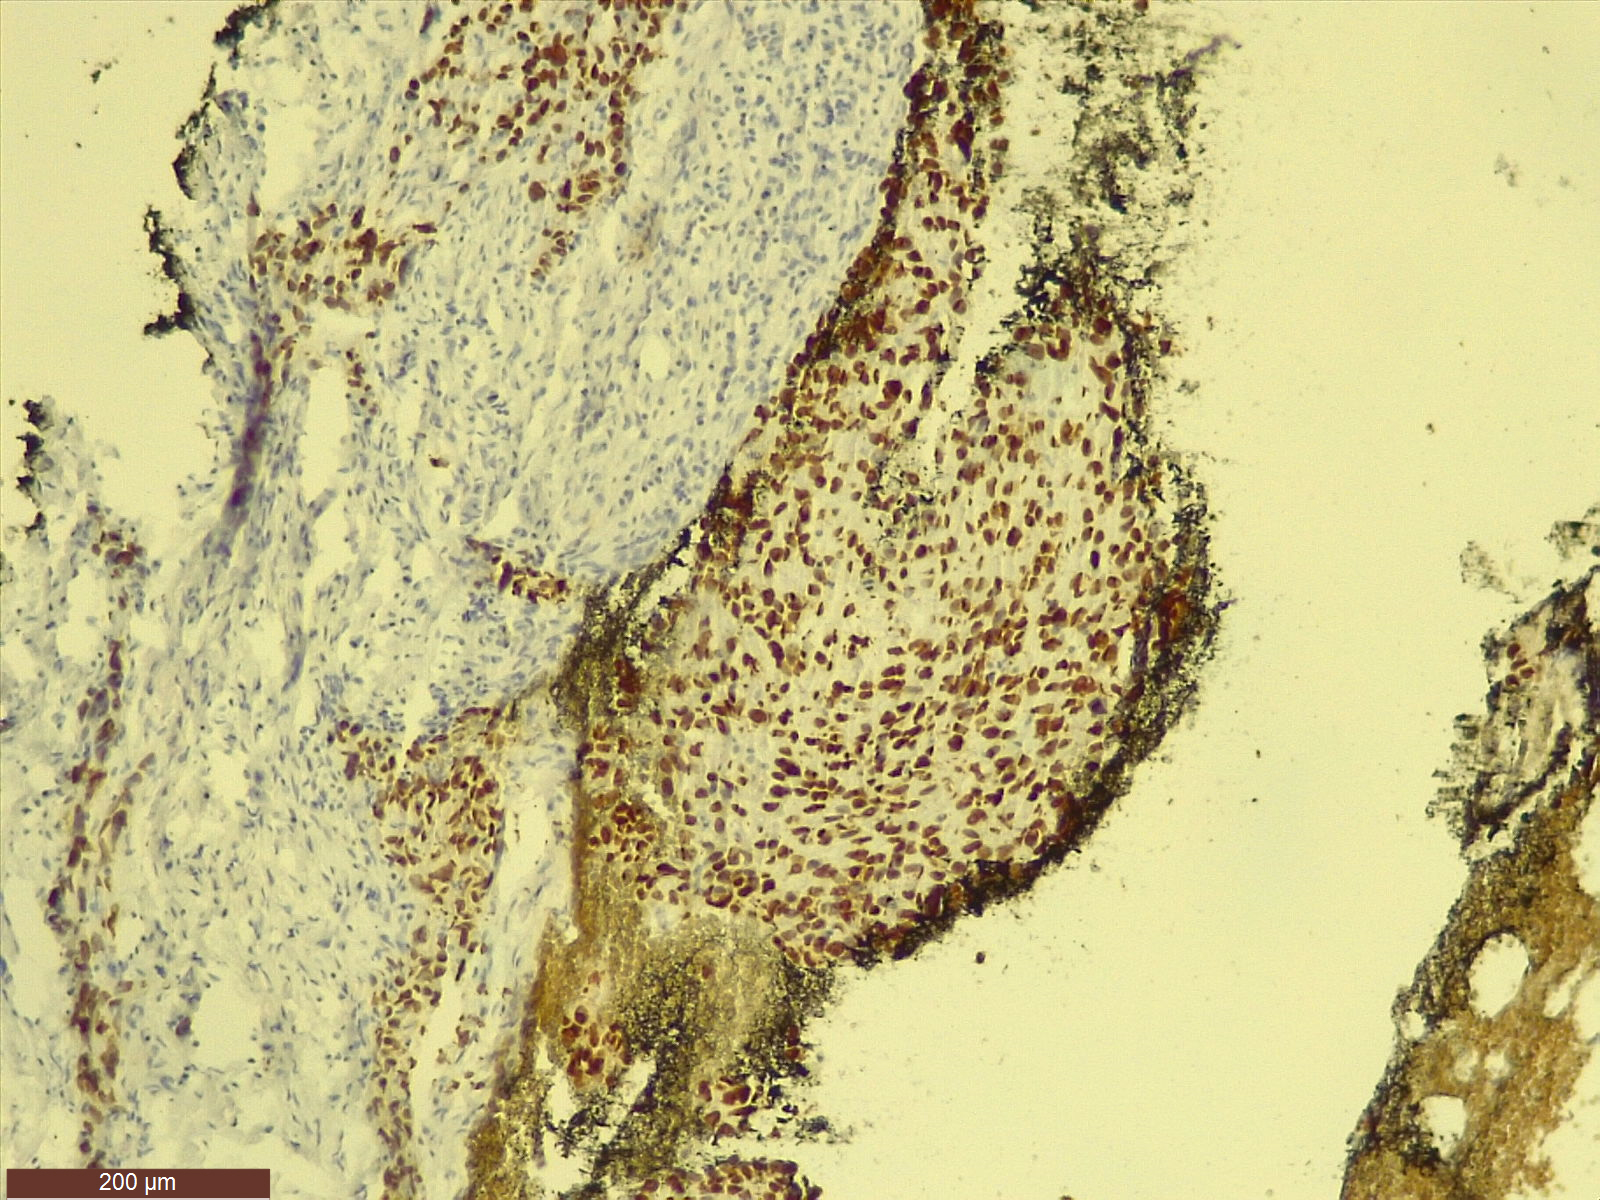

La Laboratorul de Anatomie Patologică se realizează teste de imunohistochimie (IHC) pe tumori pulmonare primare (care se dezvoltă inițial în plămân). Astfel, tumorile pot fi diferențiate rapid.

Investigația se realizează manual și permite, în urma folosirii unor reactivi, evidențierea unor molecule care ajută la definitivarea diagnosticului de cancer bronhopulmonar, ceea ce ajută ulterior la personalizarea tratamentului.

foto: Spitalul Victor Babeș Timișoara

„Când vorbim de imunohistochimie (IHC), vorbim de metode de diagnostic care combină tehnica histologică cu cea imunologică și cu biochimia. Practic, IHC-ul este o analiză de laborator care vine în completarea examenului histopatologic. Acesta din urmă stabilește că este vorba de o tumoră, iar imunohistochimia ne dă informații despre caracterul sau tipul formațiunii maligne. În funcție de rezultat, de tipul de tumoră, se administrează tratamentul. Este un proces de diagnosticare în mai mulți pași prin care se identifică markerii tumorali”, explică dr. Gheorghe-Emilian Olteanu, medic specialist anatomie patologică la Spitalul Victor Babeș Timișoara.

Primul pas pentru realizarea acestei analize este prelevarea unui fragment de țesut tumoral, prin biopsie pulmonară. Acestea vor fi inițial analizate sub microscop, apoi supuse investigației IHC.